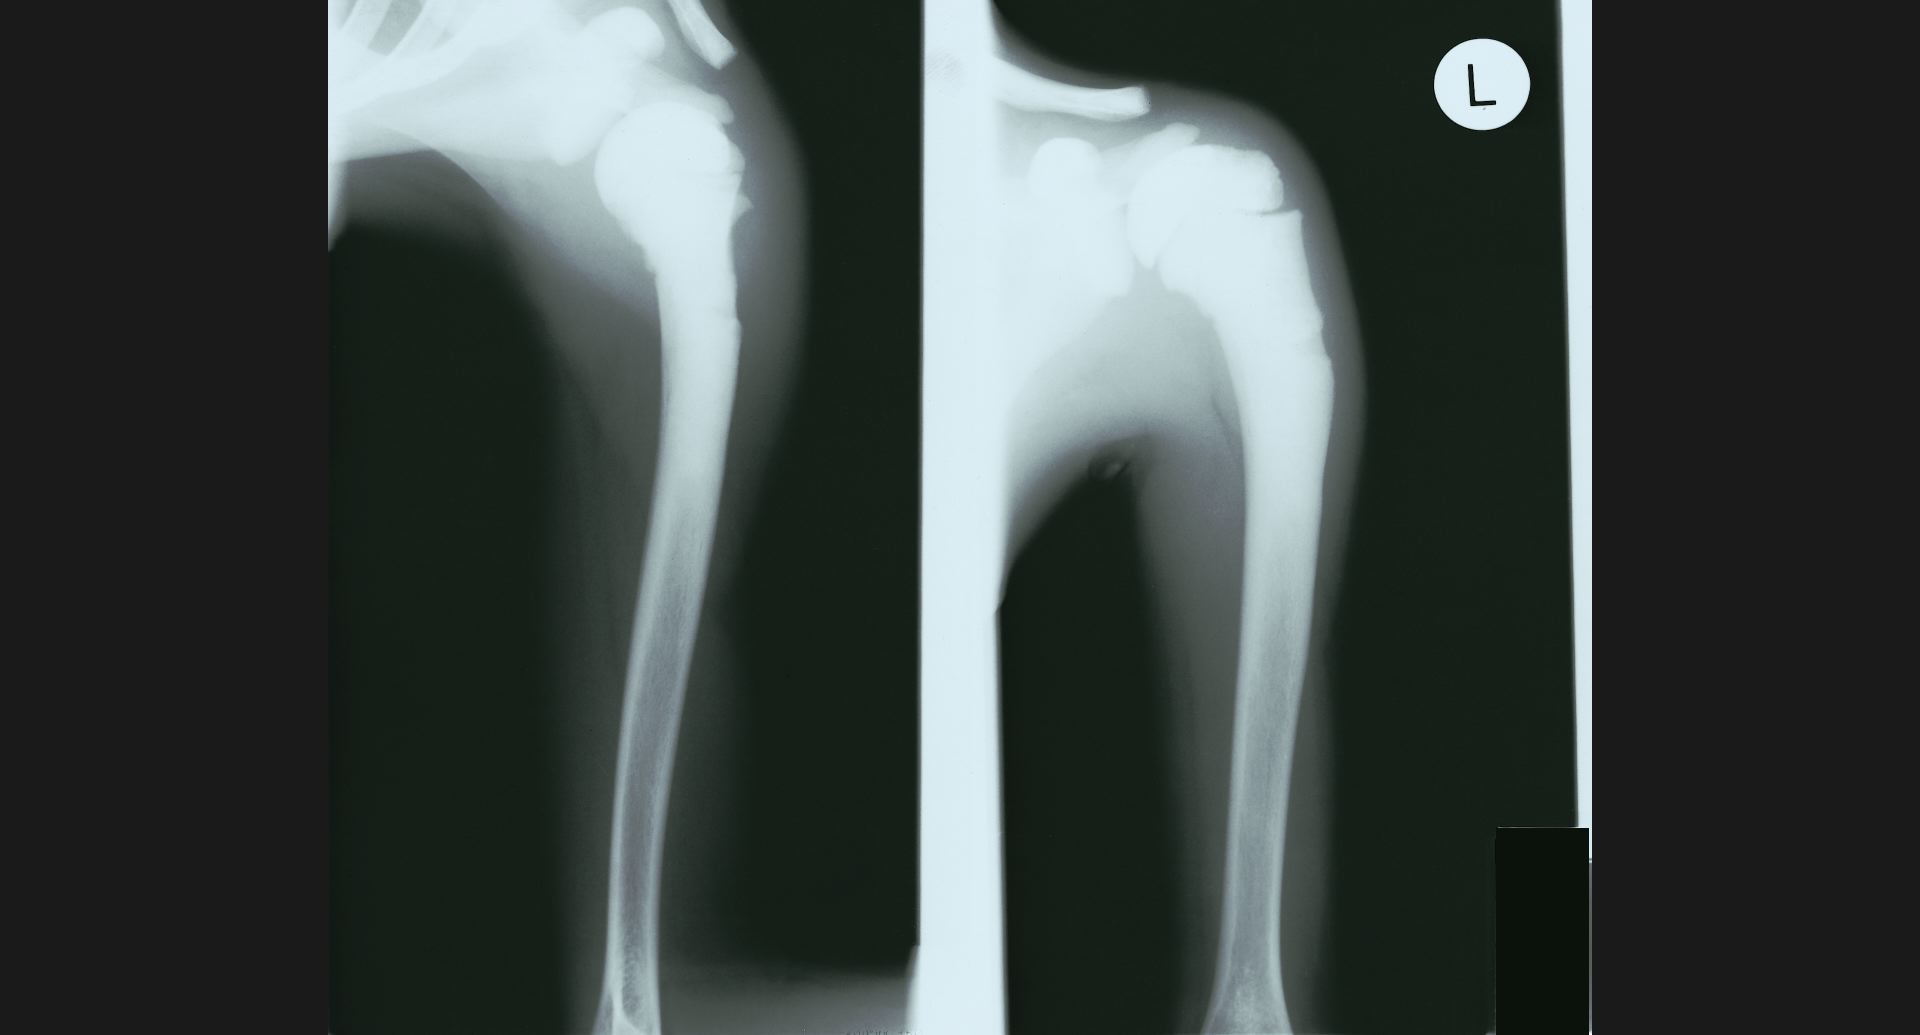

fig.16(93KB)

:Osteoblastic metastases (骨盤)